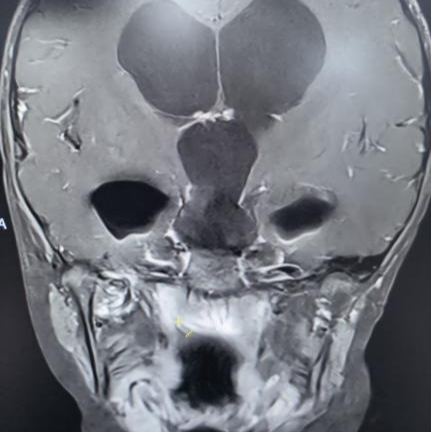

术后垂体MRI增强检查

手术中,团队借助高清4K神经内镜,凭借精湛的显微操作技术,细致分离肿瘤与周围神经、血管的粘连。历经3小时,肿瘤被完整切除,下丘脑、垂体柄、视神经等重要结构均得到完好保护。术后病理确诊为颅咽管瘤。